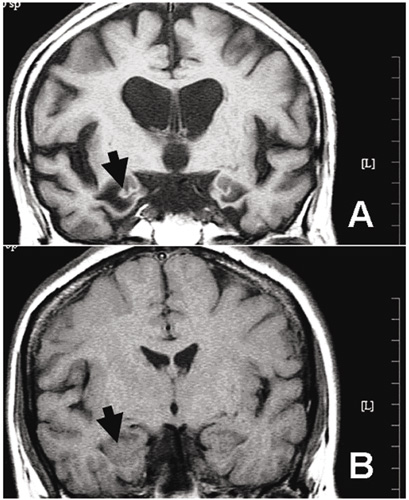

從磁振造影圖中,可以明顯看出失智症患者的海馬迴(箭頭所指處)萎縮。

失智症主要是類澱粉斑塊沈積在大腦皮質和海馬迴中,造成神經原受損所致。從阿茲海默症患者腦部病理切片,可以發現「神經微纖維纏結」和「老年斑塊」、細胞空泡等特徵。而這些發生在大腦中的病變,可能早在出現明顯症狀前的三、四十年前就已開始。